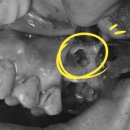

역곡더맑은치과의원

서울훈치과의원 역곡 부천 소사구의 서울훈치과의원은 역곡역 1번 출구에서 가까운 위치에 자리 잡고 있습니다. 이곳은 대학병원 협력 병원으로서 수준 높은 진료를 제공한다는 장점이 있습니다. 대중교통을...

역곡 임플란트 | 고난도 뼈이식 전문 서울훈치과(20260217)

과잉진료나 치료비용이 무서워서 미룬 분들도 많을 것 같아요 그런 분들을 위해 추~천 드리는 #역곡치과 #역곡치과추천 역곡 더맑은치과입니다! 이곳 치과 장점! 1. 과잉진료가 절대 없다!&양심적 가격! ->충치가...

이클래스 역곡에 위치한 서울파트너치과의원이 도움이 될 수 있을 것입니다 일단 이곳은 가톨릭대학교 성심교정과 인접해 있어 지역 주민과 직장인들에게 편리한 의료 서비스를 제공하고 있는데요 내원하는...

역곡 뉴욕탑치과의원은 환자의 구강 건강을 최우선으로 생각하는 치과 전문 의료기관이다. 최신 장비와 체계적인 진료 시스템을 갖추고 있어, 치과 치료에 대한 두려움을 줄이고 만족도를 높이는 것을 목표로...

치아 건강은 정말 중요한 부분 중 하나죠 제가 소개해드리는 곳은 서울파트너치과의원이에요 역곡역 2번 출구에서 위치한 치과입니다 분과별로 6인의 전문의가 진료하고 있답니다 100평 규모의 진료공간과...